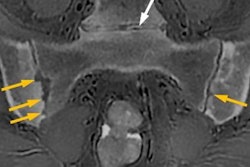

The needle is a critical component of the Arrow EZ-IO intraosseous vascular system, which can be used when intravenous access is difficult or impossible to obtain in emergent, urgent, or medically necessary cases, according to the vendor. With the new MR-conditional labeling, clinicians can now continuously care for patients who require MRI scans without interruption to the established site for vascular access, Teleflex said.